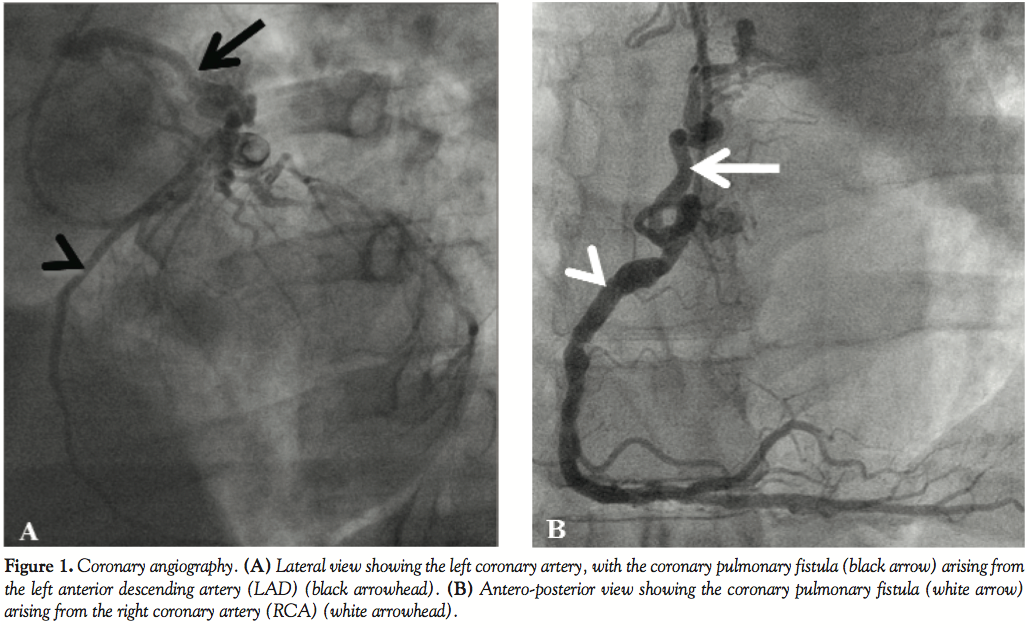

Case Report. A 48-year-old man with no past medical history was transferred to our institution with an acute inferior STEMI. He was directly transferred from the ambulance to the catheterization laboratory for a primary percutaneous coronary intervention (PCI). The coronary angiography revealed an acute thrombotic occlusion of the mid-portion of the RCA, which could be successfully treated by thromboaspiration and bare-metal stent placement. The coronary angiography also showed significant stenoses of the LAD and LCX arteries. Moreover, it revealed the presence of 2 large coronary artery fistulas, one originating from the proximal LAD (Figure 1A) and the other from the ostial RCA (Figure 1B), both draining into the pulmonary trunk at 2 different, but close, entry sites. In the acute setting, no right heart catheterization was performed. The fistulas were subsequently imaged by coronary computed tomography (CT) scan (Figures 2A–2B) and transthoracic echocardiography (TTE; Figure 3).The creatinine kinase level reached a maximum of 1,500 U/L, and the TTE performed before discharge showed a preserved ejection fraction (60%) with a mild inferior hypokinesis, normal size of the right atrium and right ventricle, and no pulmonary hypertension. After consideration of anatomy and extension of the remaining coronary stenoses and according to the wishes of the patient, the surgical treatment option (coronary bypass grafting and fistula ligation) was chosen. The clinical evolution was uneventful, and the patient was discharged on dual-antiplatelet therapy for 1 month. Following discontinuation of clopidogrel, the patient underwent coronary bypass grafting procedure for the LAD and LCX stenoses and ligation of the coronary artery fistulas 6 weeks after stent implantation.